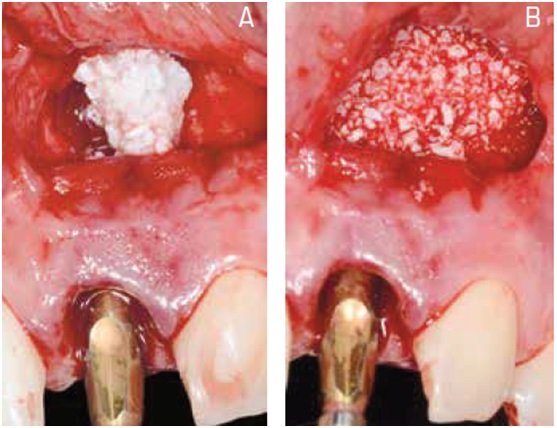

O tratamento consistiu na extração atraumática do dente e incisão de acesso na região periapical, para facilitar o procedimento de debridamento e minimizar o trauma mecânico na região cervical. Após remoção superficial do osso infectado e curetagem da região, um implante foi imediatamente instalado e a região apical foi preenchida com hidroxiapatita sintética para recuperar o volume perdido. No mesmo dia, uma provisória apoiada nos dentes adjacentes foi instalada e, após cinco meses, o paciente recebeu tratamento protético definitivo. Considerações sobre aspectos teóricos e práticos do procedimento são apresentadas e discutidas, com ênfase na previsibilidade estética do tratamento.